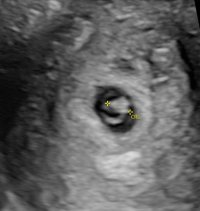

Ble dessverre satt tilbake fra 6+5 til 6+0, noe som er litt rart med tanke på stabil syklus, men da tok det vel litt tid fra EL til befruktning.